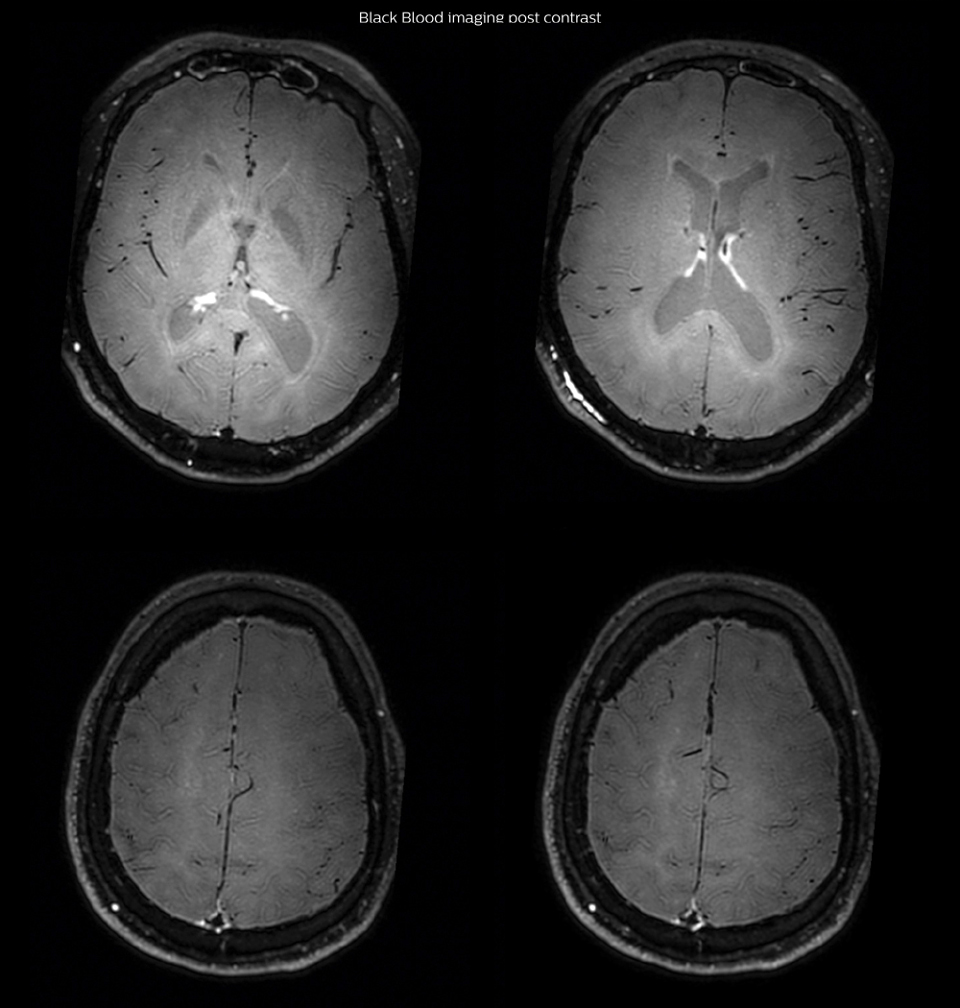

Arrows show vessel wall enhancement which appears concentric and homogeneous in different cerebral territories.

So, we decided to perform Black Blood imaging. The presence

and the pattern of vessel wall enhancement on Black Blood

imaging, can help us to determine the etiology of the lesion.

Many studies have shown that Black Blood imaging can help

differentiate vasculitis from other causes of vasculopathy, such as

atherosclerosis, with a high specificity [1-3]. In an atherosclerotic

lesion, vessel wall thickening and enhancement are usually eccentric,

while in vasculitis the wall thickening and enhancement are usually

concentric, homogenous, and in a long portion of the vessel.

In this case the Black Blood imaging helped us to suggest the

diagnosis of HIV-related brain vasculitis.

One month after beginning the antiviral treatment, the same

MRI examination was repeated and again 8 months after the

beginning of treatment. On follow-up images, we see the

enhancements have almost disappeared.

After one month of treatment, post-contrast Black Blood images at the exact same levels as in the figure above show disappearance of the vessel wall enhancements which were seen on the previous examination.